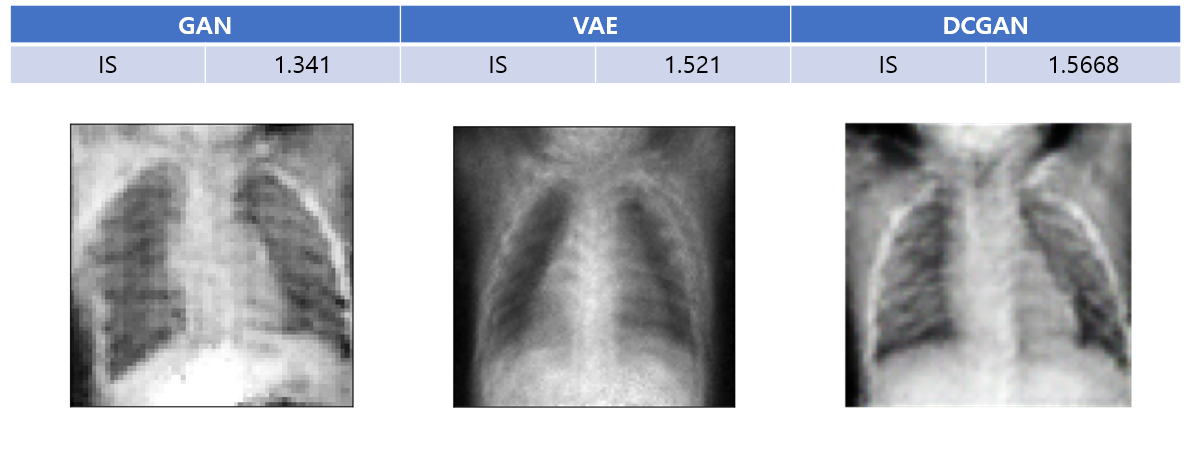

Kaggle에서 제공해주는 데이터셋인 chest X-ray 이미지를 가지고 총 1341장을 사용해 흉부 x선 이미지를 학습시켰다. 모델은 세 가지 생성모델인, GAN, DCGAN, VAE를 사용하였다. 학습 이후 30장의 X-ray 이미지를 생성한 후 IS를 측정해보았다. DCGAN이 성능이 가장 좋았으며 VAE는 아무래도 autoencoder를 사용하다보니 생성된 사진이 흐릿한 경향이 있었다.